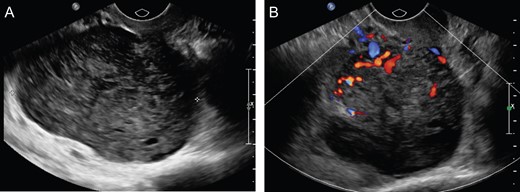

While awaiting evaluation by gynecologic oncology, she presented acutely with nausea, vomiting and abdominal pain. At that time, she was found to have a small bowel obstruction (SBO) on CT imaging with concern for a transition point near her previously visualized pelvic mass (Fig. 2). She was given a trial of non-operative management, including nothing by mouth and nasogastric decompression; however, given her persistent abdominal pain and high nasogastric tube (NGT) output, it was thought best to proceed with operative intervention.

(A) Dilated small intestine with small amount of ascites. (B) Large heterogeneous pelvic mass. (C) Coronal view pelvic mass (arrow) with compression of bladder (arrow head). (D) Sagittal view pelvic mass.